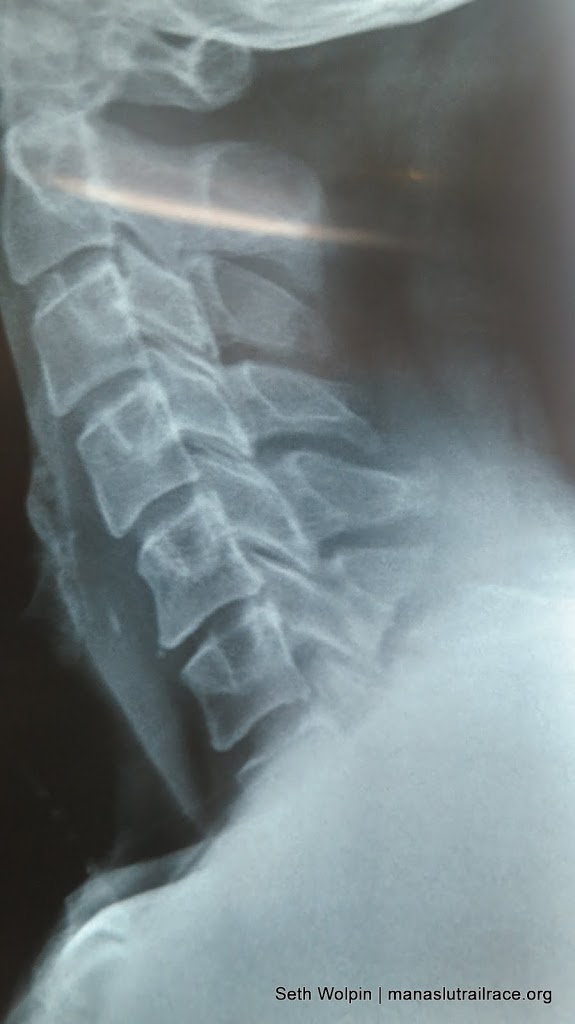

Back in Kathmandu, the news is not so great. I’ve been on the MRI circuit. It looks like a posterior fracture on C7 and there is some other stuff going on as well. But in all likelihood it will all heal on its own, I just need to stop running for a while and ‘take it easy’. Will do as I am going to Thailand tomorrow for John and Kathleen’s wedding. They have resumed their world tour! Just park me under a palm tree, I’ll be the dork on the beach with the cervical collar.